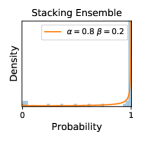

5.1 Distribution of Uncertainty Scores

Distribution of Uncertainty Scores Across Different Severity Levels As explained in Section 3, each uncertainty metric essentially defines an order/ranking among the data points. We conducted an analysis to better understand what data will be assigned high uncertainty under a particular uncertainty metric . Picking out the highest ranked data points (), we calculated the ratio of data points from each SL. Figure 4 summarizes the results as box plots for the Kaggle-DR and the Messidor-2 datasets; additional detailed statistics can be found in Table S.1 in the supplementary materials. From the plot and table, SL1 & SL2 examples account for a higher proportion among the top-ranked uncertain examples across the three ensemble methods. This finding matches our intuition that incipient disease examples (SL1 & SL2) are more likely to be considered uncertain by ensemble methods due to their ambiguity.

In contrast, the MC-dropout method showed the worst overall performance among the three, as it can be seen from the high ratios of SL0 examples among the uncertain negatives in Figure 4. The histograms in Figure 2 provides another perspective to look into the phenomenon, where a decent proportion of MC-dropout model’s predictions on SL0 inputs entailed low confidence (far from 0 or 1), which from another angle explained why MC-dropout was less specific in terms of lower FNP; many no-DR inputs (i.e. SL0) were erroneously assigned high uncertainty by MC-dropout models.

It is still an open question why the evaluated MC-dropout networks signaled relatively high uncertainty on SL0 & SL3 & SL4 data that are less likely to be ambiguous. We conjecture that much of the “uncertainty” indicated by disagreement among test-time dropout samples actually reflects the stochastic nature of dropout networks rather than the real decision uncertainty associated with the data. It is worth noting that the MC-dropout model we evaluated was not weak per se; they all achieved above Area Under Curve (AUC) scores on test sets. The weakness of individual test-time samples (which explains their low-confidence predictions on SL0 & SL3 & SL4) might have been hidden when they are aggregated into an ensemble—a well-known advantage of ensemble learning. Our results suggested that the uncertainty information given by implicit ensemble methods such as MC-dropout and TTA might not be as reliable as that from explicit ensemble approaches (e.g., stacking ensembles). Similar findings on MC-dropout can be found in some previous papers [1].